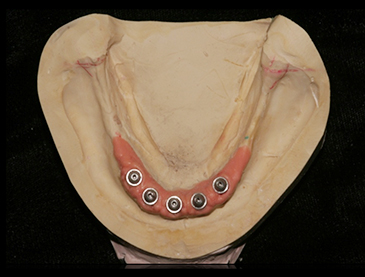

Fully edentulous clinical cases